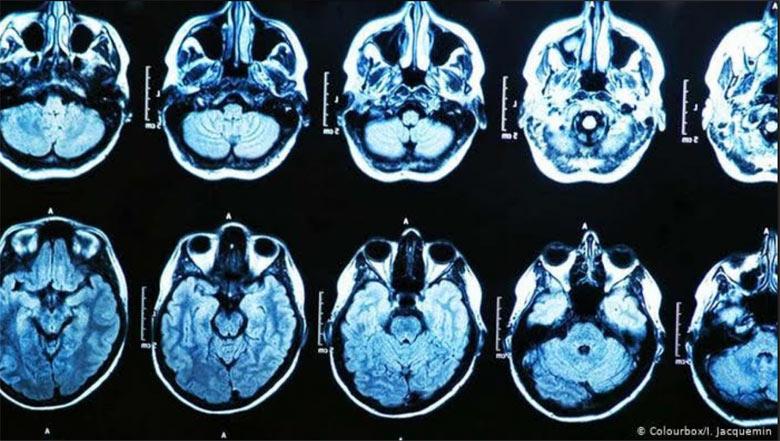

Ссылаясь на слова почти двух десятков действующих и бывших американских чиновников, там пишут о, как минимум, 130 спецагентах, дипломатов и военнослужащих, получивших черепно-мозговые травмы вследствие так называемого «Гаванского синдрома».

«Странные и необъяснимые эпизоды становились причиной травм мозга различной степени тяжести у агентов, дипломатов и даже военнослужащих, работающих на ЦРУ, Государственный департамент и Министерство обороны за последние пять лет», - говорится в статье Нью-Йорк таймс.

Там отмечают, что несмотря на то, что нападения на американцев фиксировались по всему миру, большая часть инцидентов произошла на Кубе и в Китае, а первые случаи беспричинных черепно-мозговых травм начали фиксироваться еще в 2016 году.